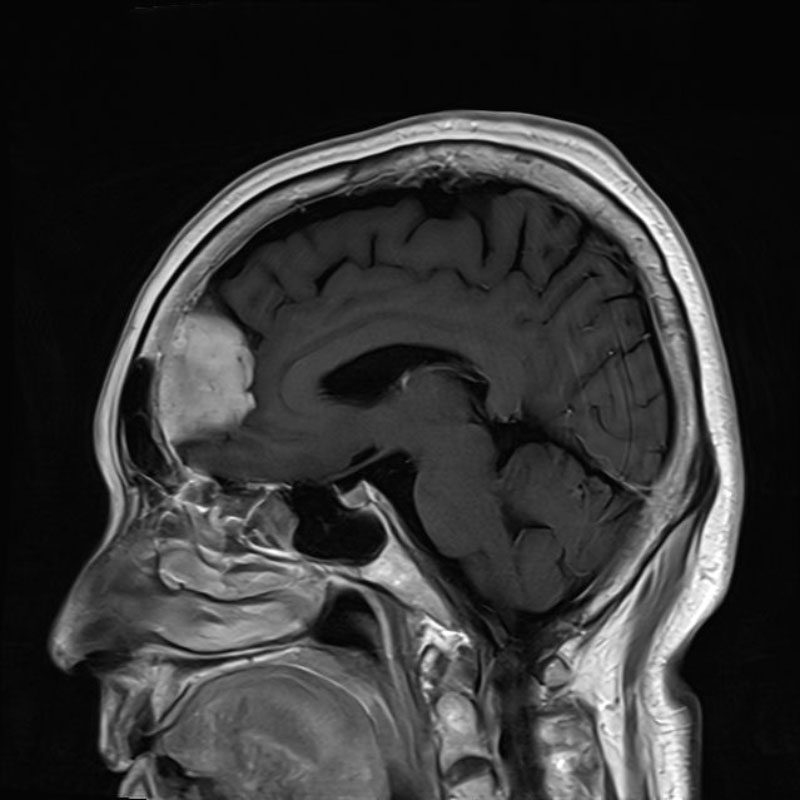

断層撮影

手術前1

手術前2